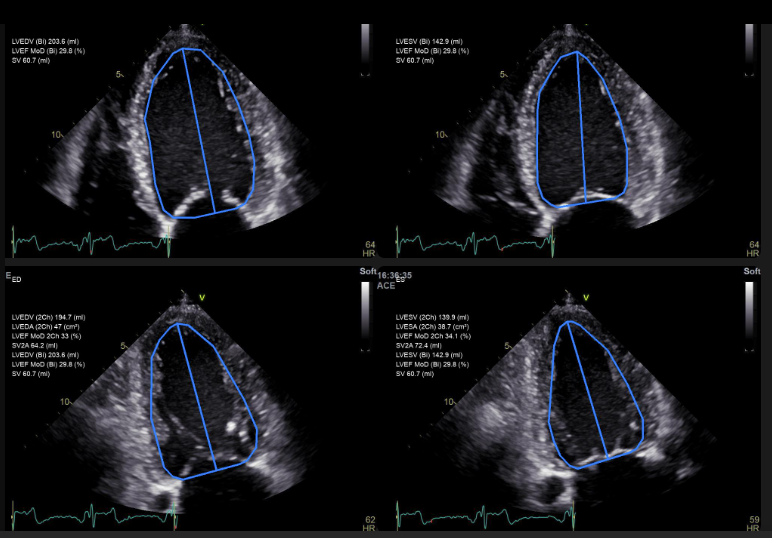

AI successfully automates heart chamber quantification during stress echocardiography

Validating AI for fully automated LV mass measurement in echocardiography

AI matches expert accuracy in assessing LV diastolic dysfunction

AI outperforms experts in LV mass assessment: new JACC study

Historic Milestone in Echocardiography: AI Surpasses Humans